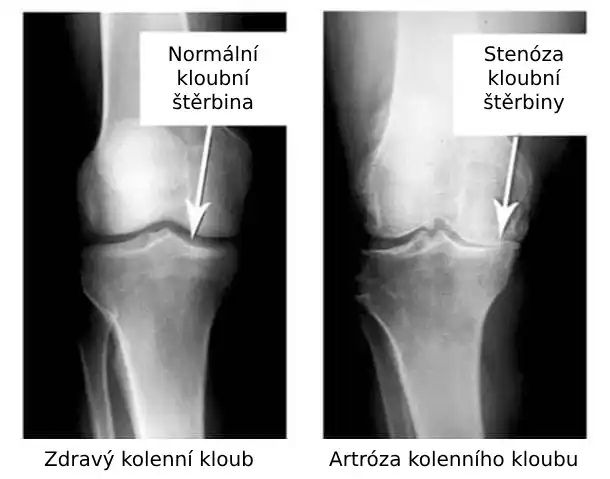

Podívejte se na tyto obrázky, můžete vidět, že na obrázku vpravo není žádný kloubní prostor, kosti se o sebe třou a způsobují silnou bolest. A tento proces je velmi těžké zastavit! Za pár let se ten člověk stane invalidním a už se nebude schopen sám živit.